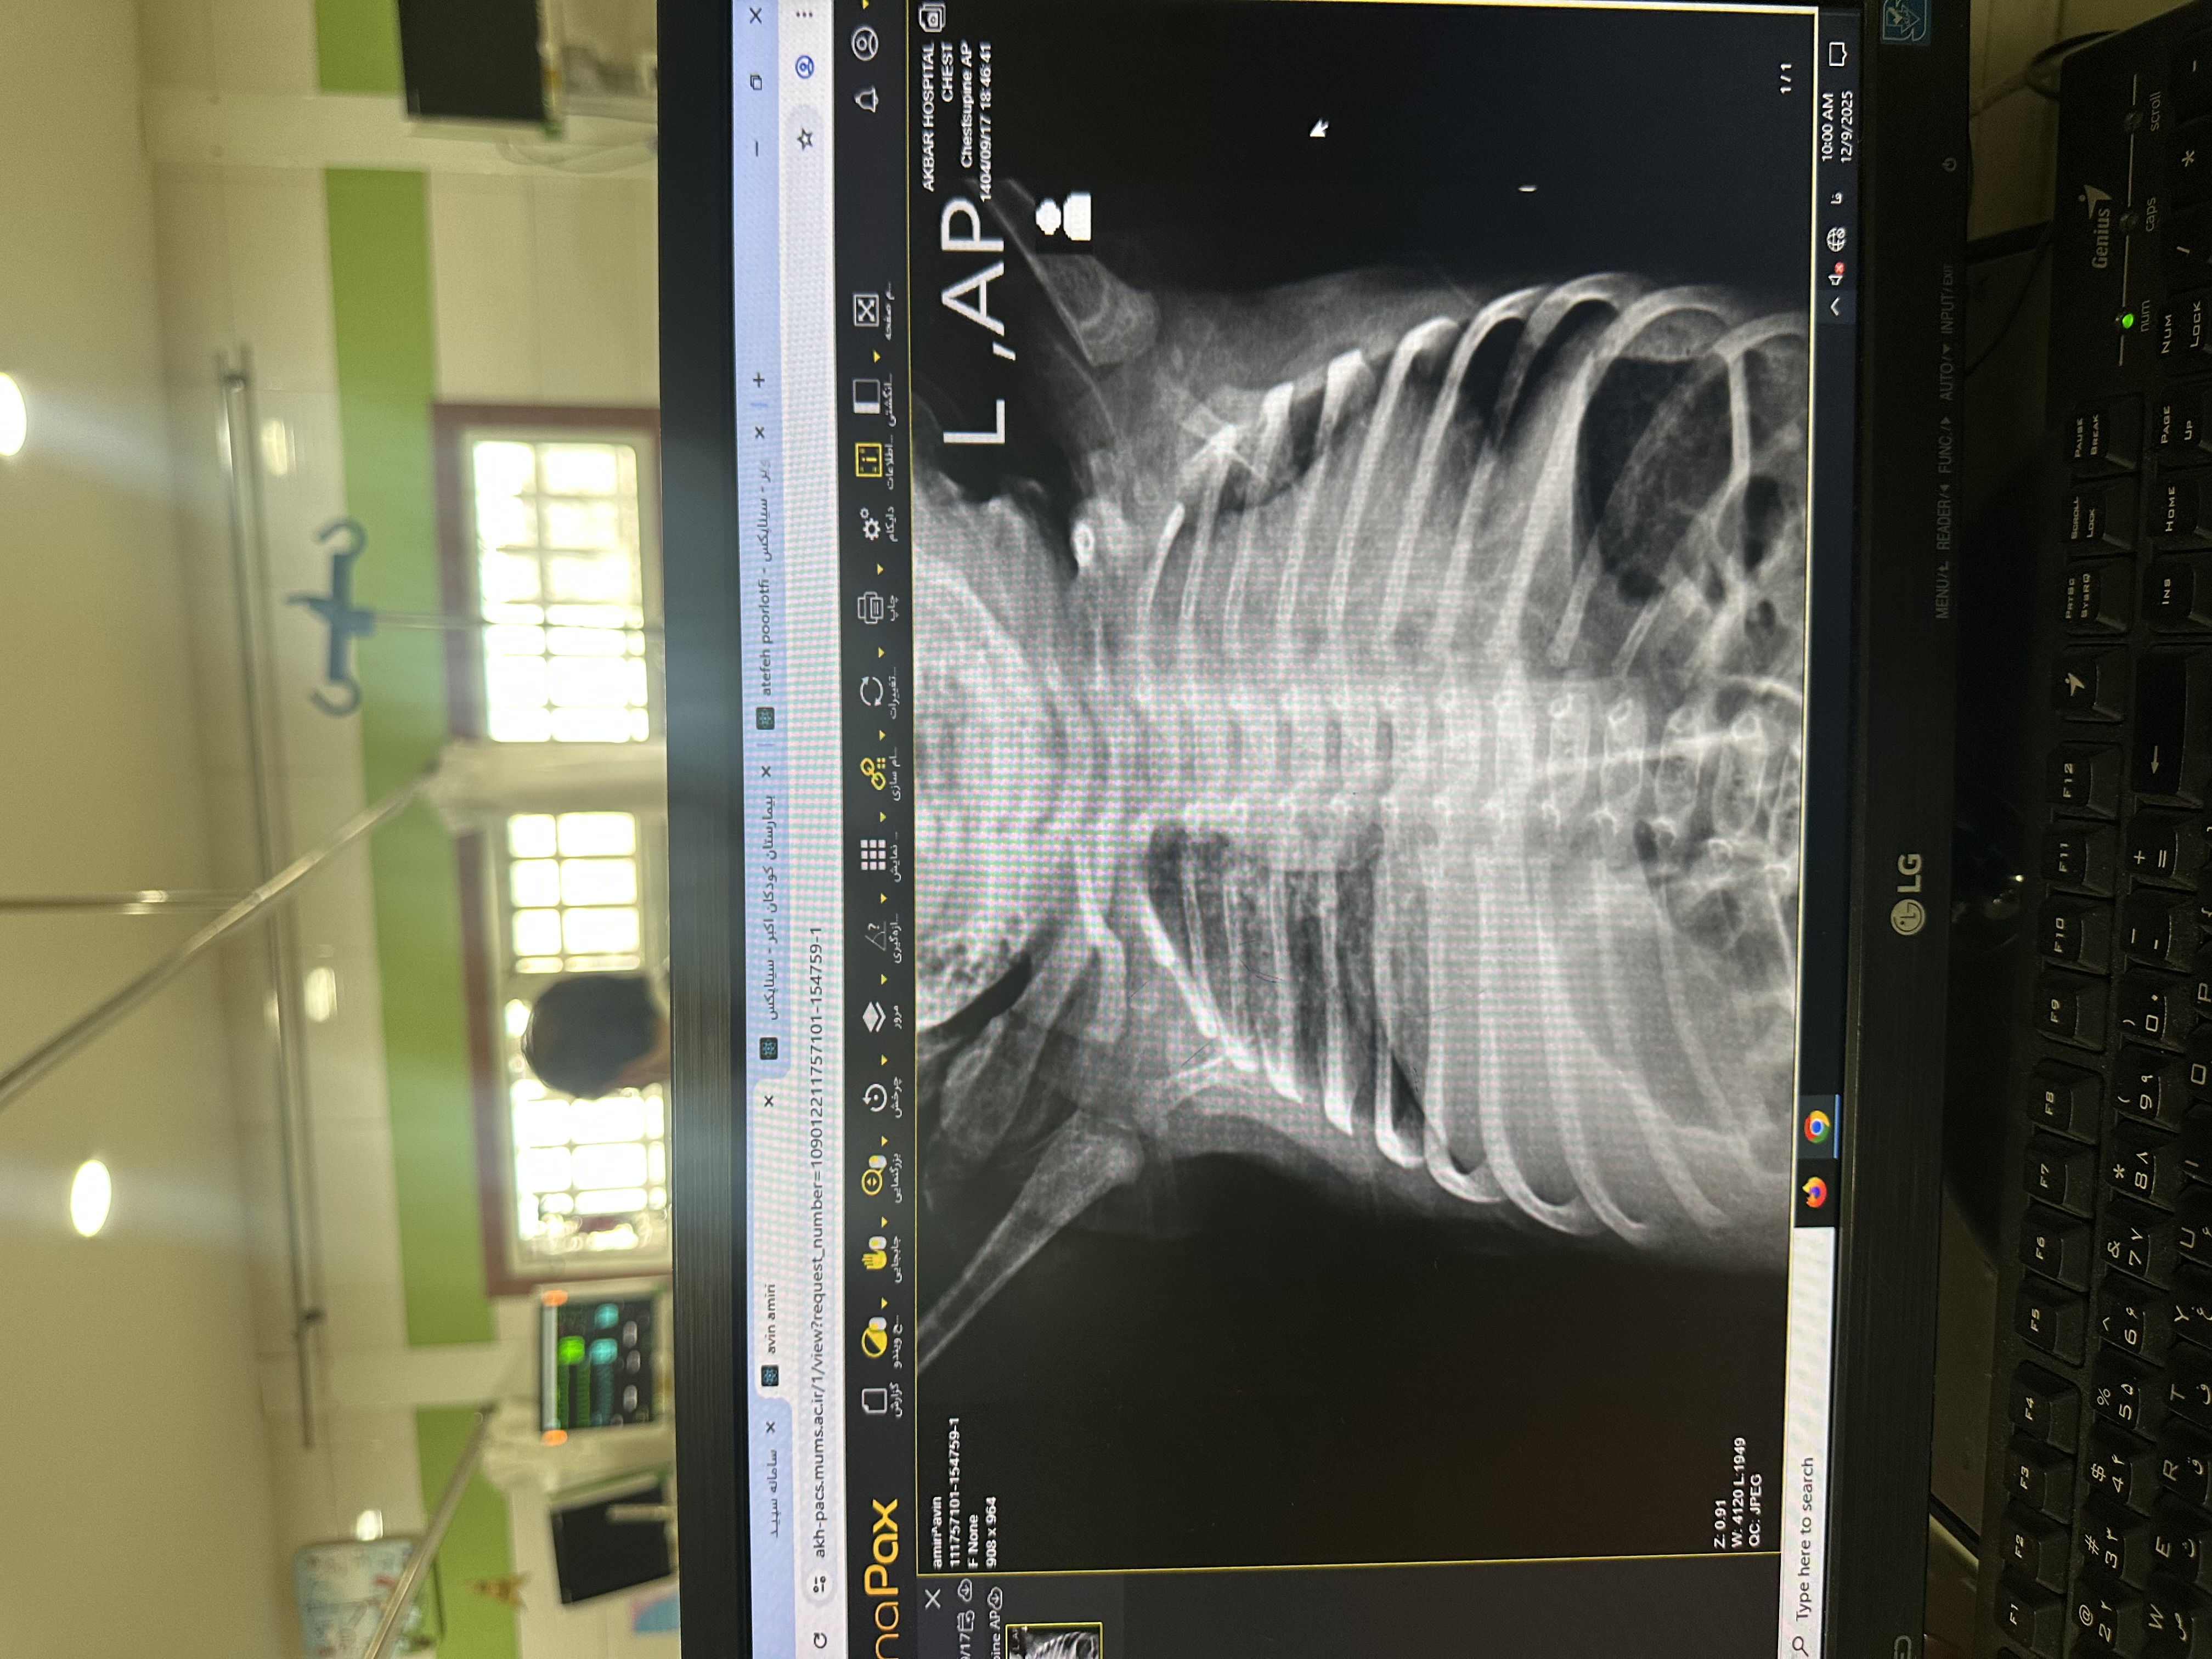

درگیری ریه راست(infiltration prihilar)

X-Ray: